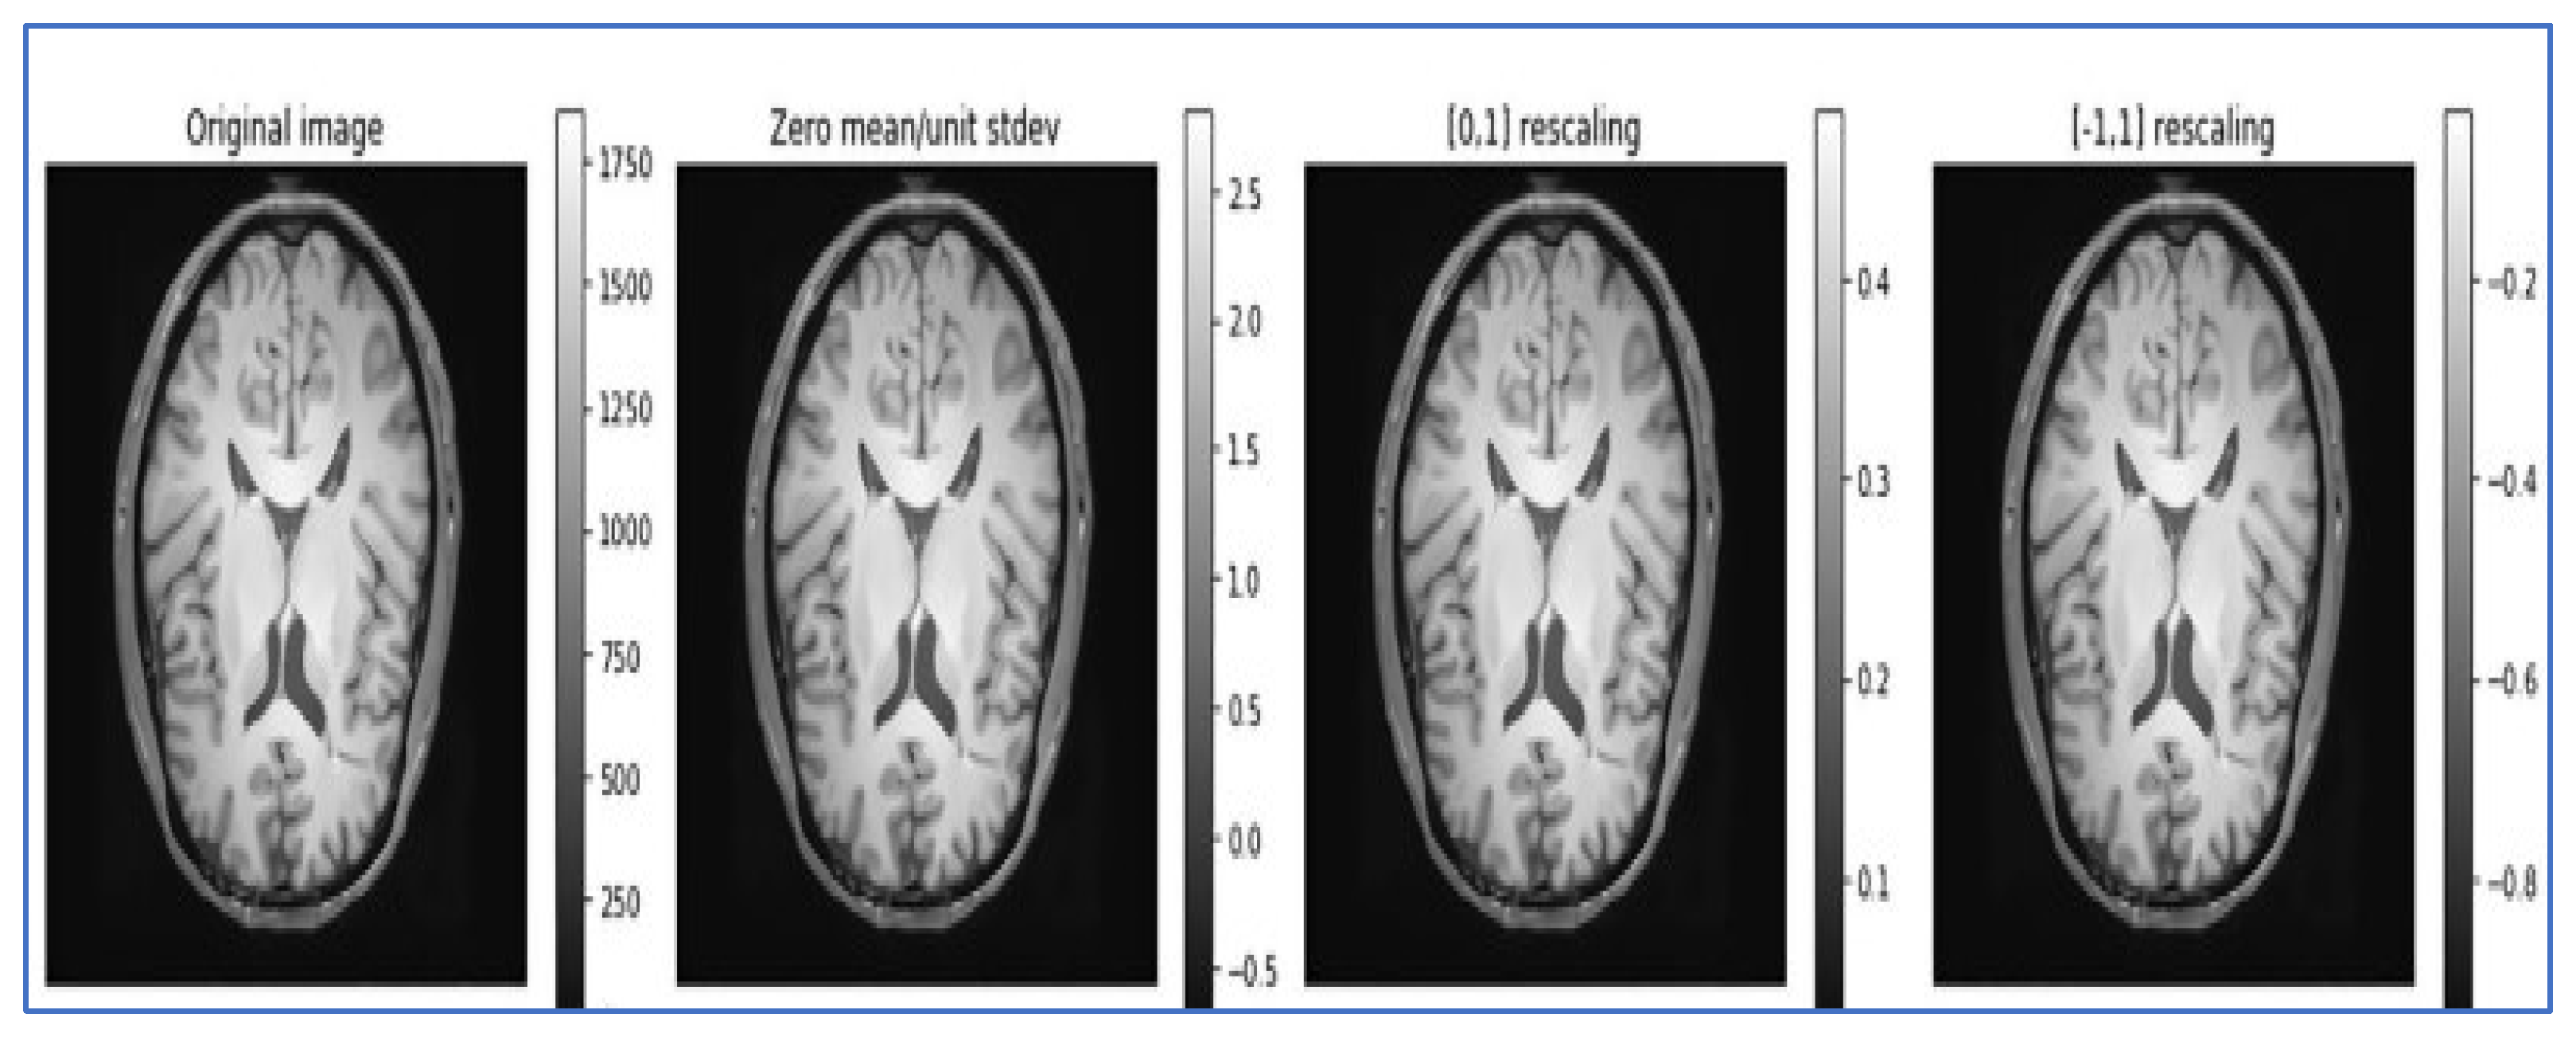

- Data normalization: Data normalization is beneficial for removing different redundancies from the datasets, such as varied contrasts and varied subject poses, to simplify subtle difference detection. It rescales the attributes with a mean value of 0 and a standard deviation of 1. Different types of normalization techniques, such as Z normalization, called standardization; min–max normalization; and unit vector normalization, are applied to the dataset. We applied unit vector normalization to our dataset.

- Unit vector normalization: It shrinks/stretches a vector and scales it to a unit length. We applied it to the whole dataset, and the transformed data are viewed as a cluster of vectors with distant trajectories on the d-dimensional unit sphere. The general formulae for unit vector normalization are , where = normalized vector, = non-Zero vector, and = length of U.